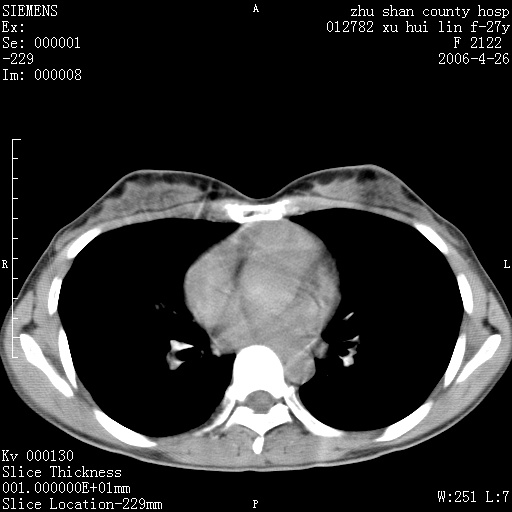

女性 病人 27岁!本院职工家属,五月前因感冒透视发现病变,ct示:左肺下叶背段感染性病变。经过半月规范抗生素治疗后复查病变无明显变化,后行四月规范抗痨治疗,复查无明显变化,后复查无效!请大家帮忙看看!

右肺下叶背段见片状高密度区,边界不清,密度不均,无钙化及空洞影,背段支气管通畅。所见层面肺门及纵隔内未见明显肿大淋巴结影。

女性 病人 27岁!本院职工家属,五月前因感冒透视发现病变,ct示:左肺下叶背段感染性病变。经过半月规范抗生素治疗后复查病变无明显变化,后行四月规范抗痨治疗,复查无明显变化,后复查无效!

诊断:首先还是考虑为慢性炎症。

病人是什么工种,从ct表现看是肺特异纤维化。

局灶机化性肺炎可能,建议她行纤支镜检查